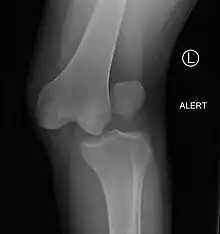

| Plain lateral X-ray of the left knee showing a posterior knee dislocation[1] | |

Plain X-rays, CT scan, ultrasonography, or MRI may help with the diagnosis.[2][11] Findings on X-ray that may be useful among those who have already reduced include a variable joint space, subluxation of the joint, or a Segond fracture.[5]